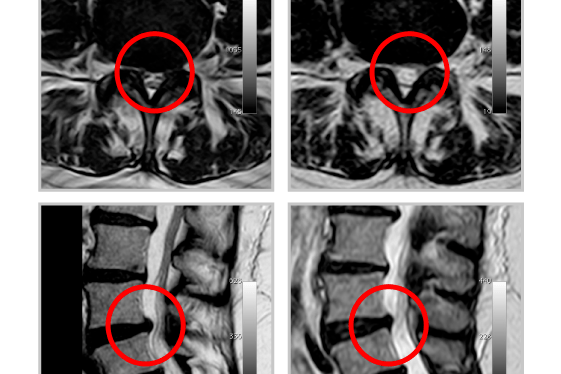

Insérer l’aiguille d’accès sous contrôle scanner dans le disque. (Vérifier le mode d'accès le plus approprié en fonction de la procédure cervicale ou thoracolombaire)